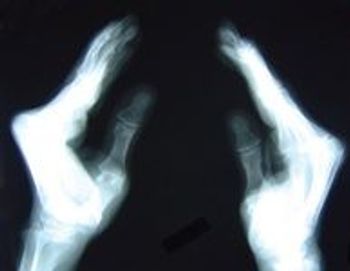

A 63-year-old woman presented with a 2-year history of bilateral hand pain and stiffness that had worsened in recent months. The pain was most severe in the fingers and was associated with morning stiffness that lasted 30 minutes. There was loss of full range of motion in some finger joints.